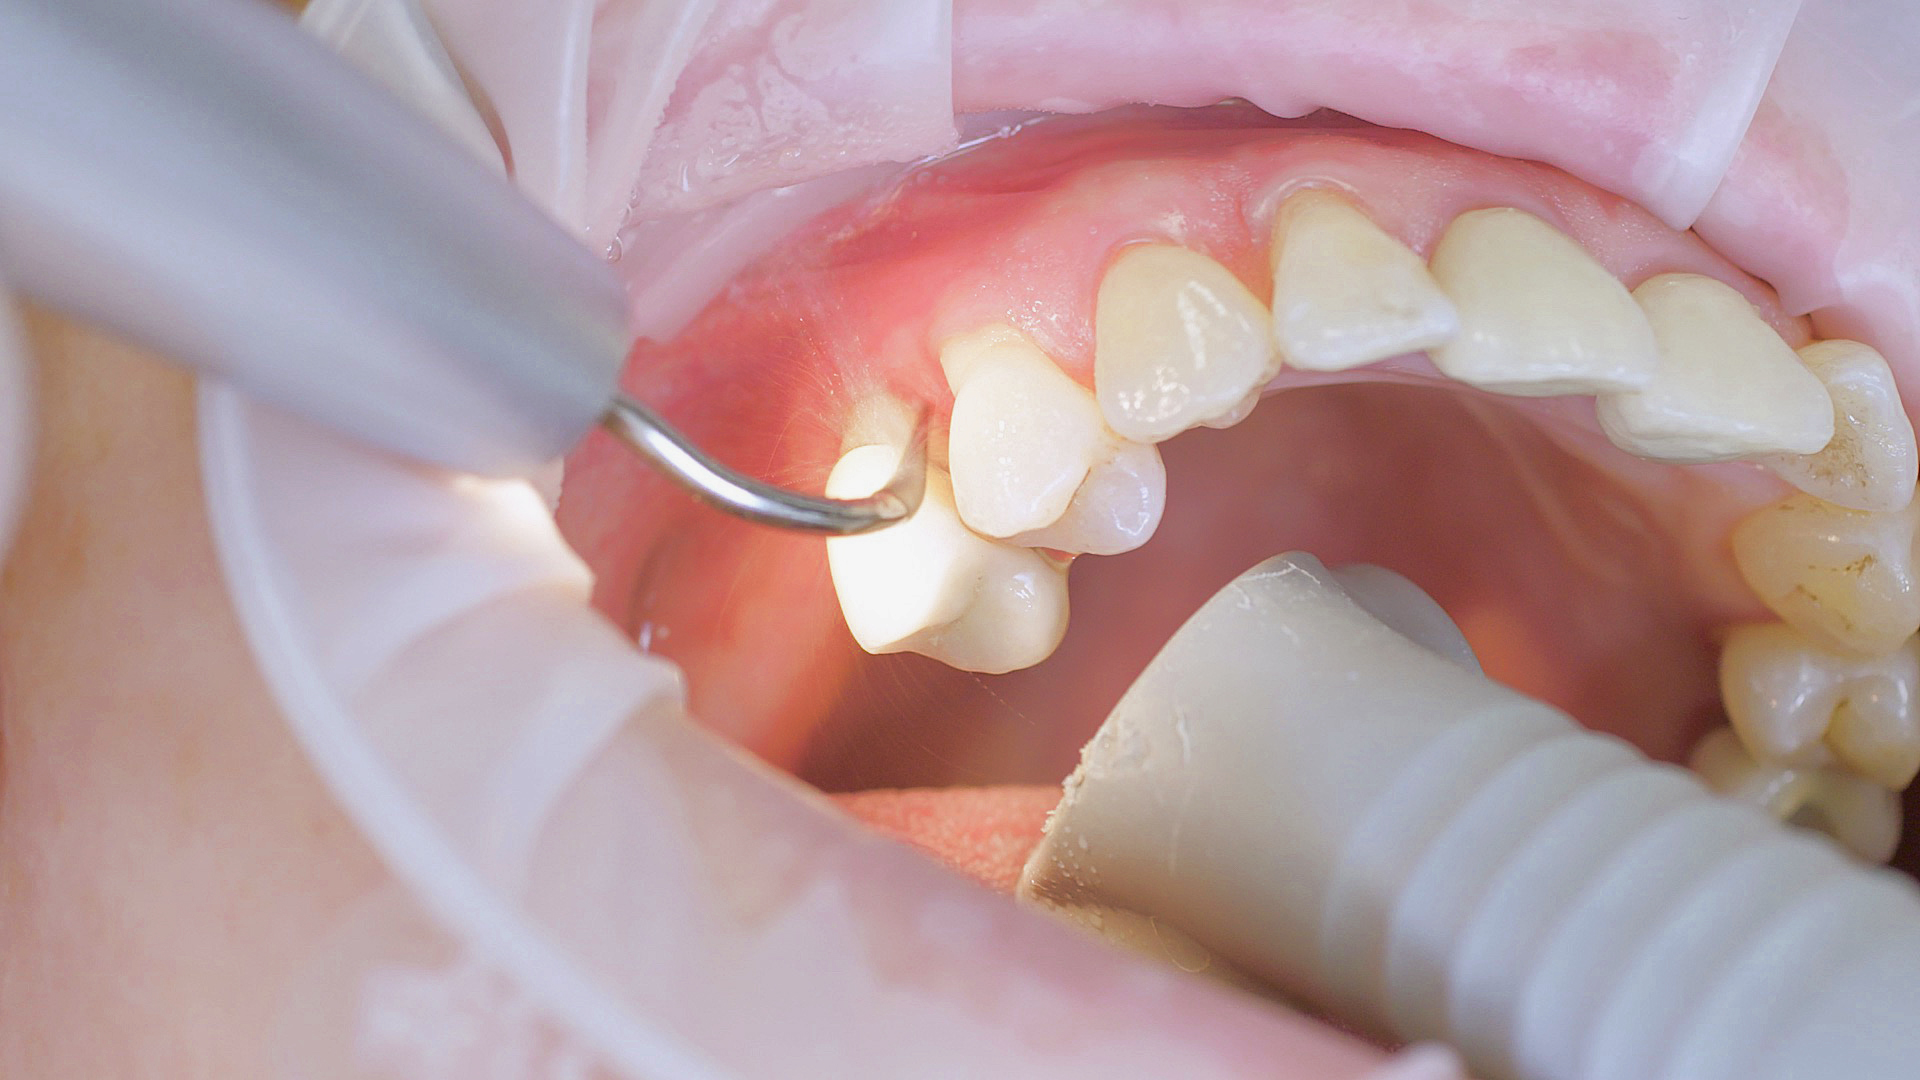

In the periodontal aftercare subsequent to implantation, soft (biofilm) and hard coatings are regularly professionally and mechanically removed.[16, 17] In the subgingival and supragingival areas, ultrasonic devices are generally used for this (Fig. 4), in combination with manual instruments where necessary. Alternatively, subgingival air polishing can be used in combination with periodontal attachments and powders.[18]

Ultrasound devices are particularly suitable for UPT

Fig. 4: Ultrasound devices are particularly suitable for UPT, for example in combination with periodontal tips (W&H Tigon+ with 1P tip)